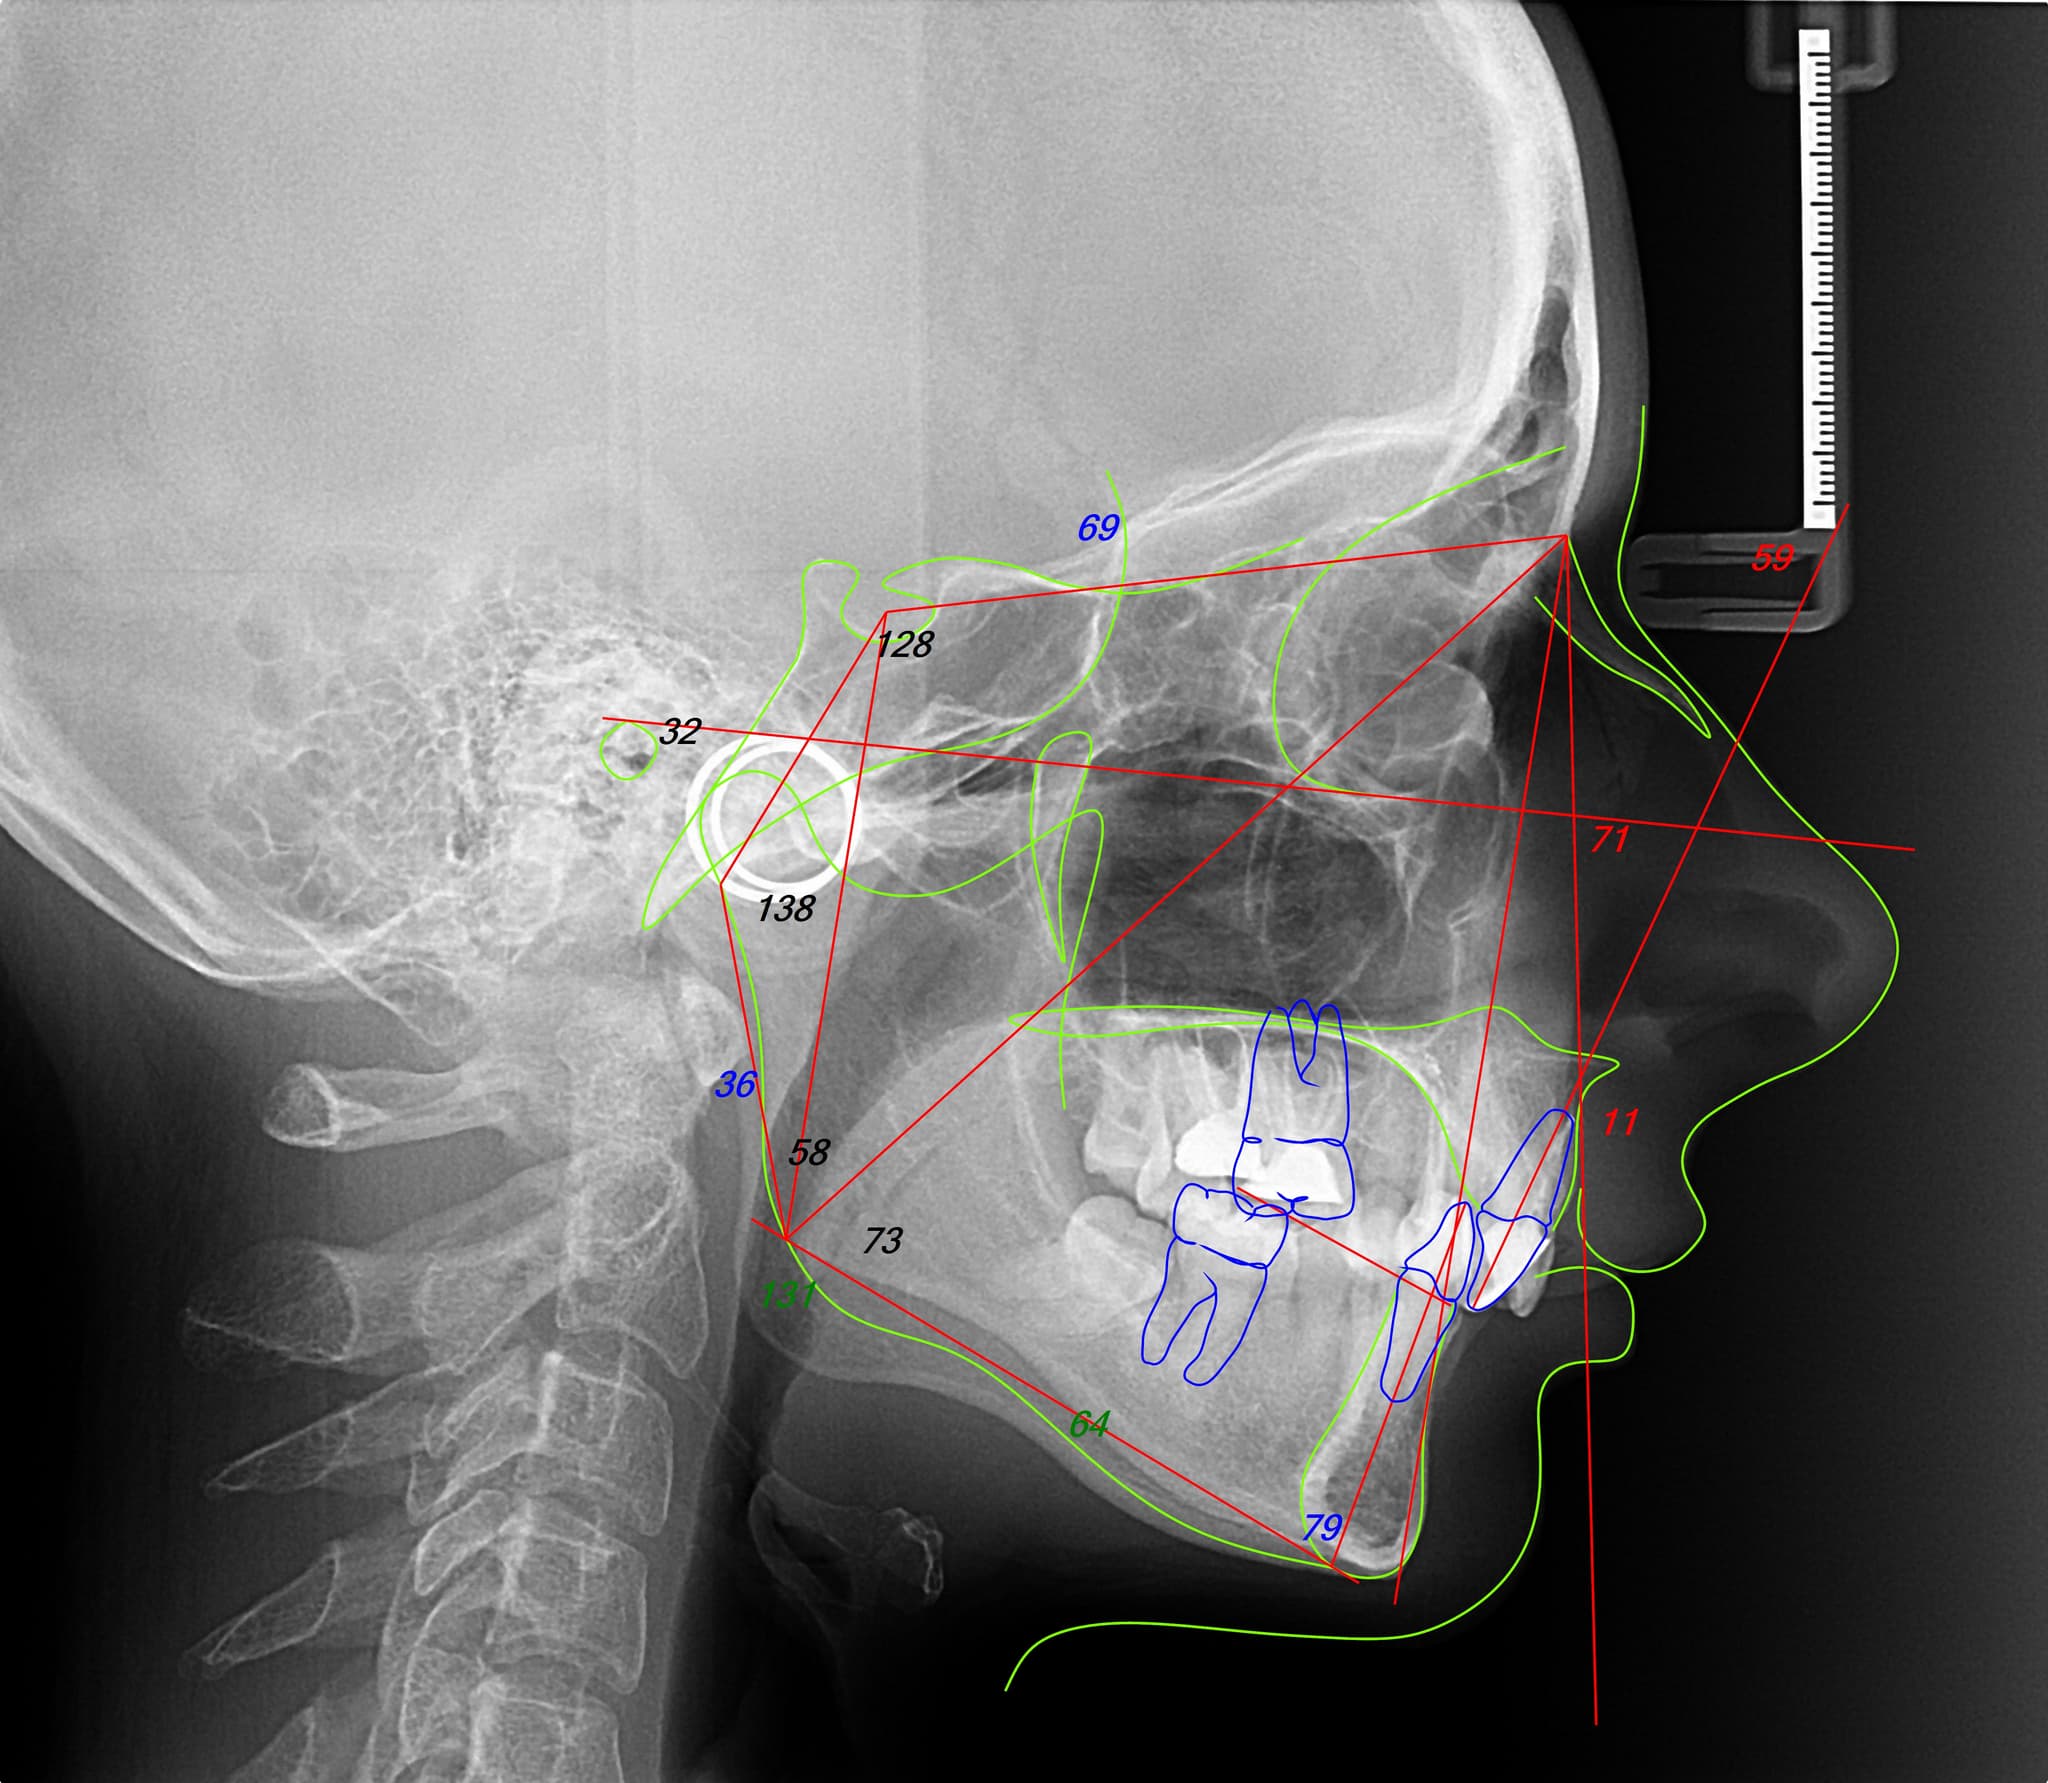

Fiecare caz ortodontic începe cu o analiză digitală completă: fotografii faciale, scanări ale ocluziei și poziția mandibulei. Pe baza acestor date, construim un plan unic interdisciplinar, aliniind ortodonția cu obiectivele generale ale tratamentului—fie ele protetice, chirurgicale sau parodontale. Această abordare stratificată, dar unitară, asigură că fiecare mișcare contribuie la un rezultat coerent și sustenabil.